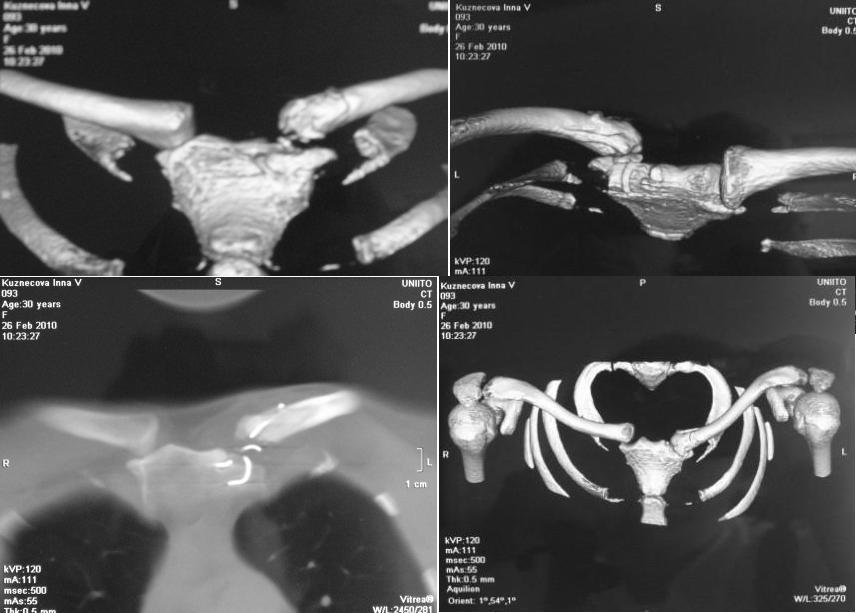

Диагноз: застарелый передневнутренний подвывих грудинного конца левой ключицы. Сросшийся перелом грудинного конца левой ключицы. Частичный дефект суставного конца левой ключицы.

На КТ от 26.02.10г. диастаз между суставной поверхностью грудины и левой ключицей составляет 0,8-0,9см.